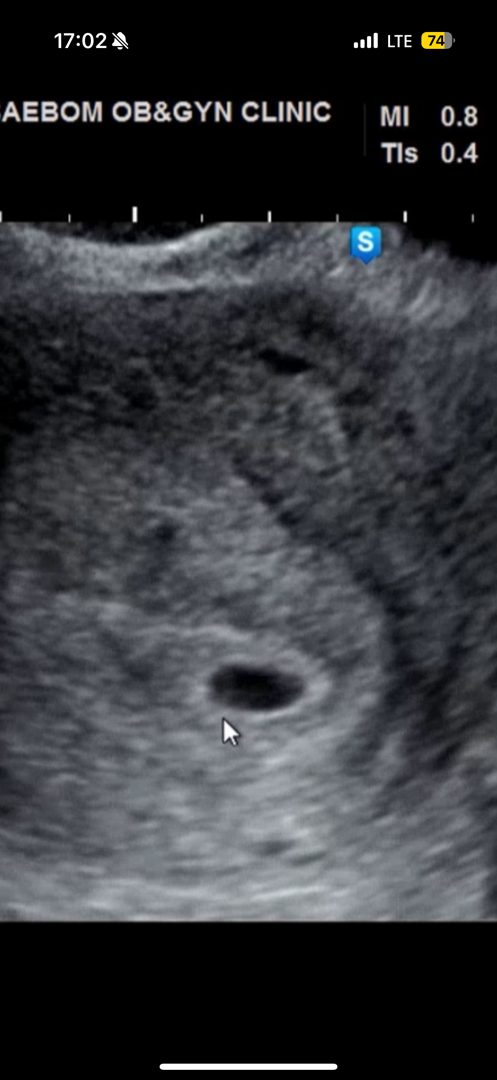

4주 6일차에 본 아기집입니다. 사이즈는 0.67 인데 난황이 있다고 따로 얘기해주시지 않으셨어요. 오늘 초음파 영상 보다가 동그란걸 발견했는데 난황처럼 보이나요?? 😭